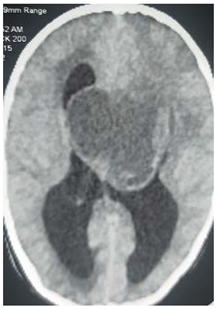

This is 50 years male, empolayer, heavy smoker, presented to neurosurgery emergency unit with history of rabidly progressing headache, unsteady gait and deterioration level of consciousness for few months duration.

On examination: obese, his GCS was 14/15, moving his limbs adequately but irritable.

Consequent to resuscitation, and clear counseling to the family, the patient prepared for surgical decompression.

Operation: through Rt par median sub occipital craniectomy, macroscopic excision of the tumor was done. The tumor was lobulated well circumscribed, less vascular and extending to the cistern magna.

Patient showed good recovery after the completion of surgery, taken to the ICU on nasal oxygen, and 48 hours released to the general word.

Histopathology

Revealed brain tuberclomata ( extra pulmonary tuberculosis)

Patient was put on anti-tuberculosis according to the program.

In the 7th day post operative, the patient developed high grade fever with respiratory distress, the diagnosis of pneumonia was made and eventually intravenous antibiotic was given, unfortunately, 3 days following he developed Rt lower limb cellulites that complicated with shortness of breath and emergency intubation was done and put on mechanical ventilation but few hours following he died.